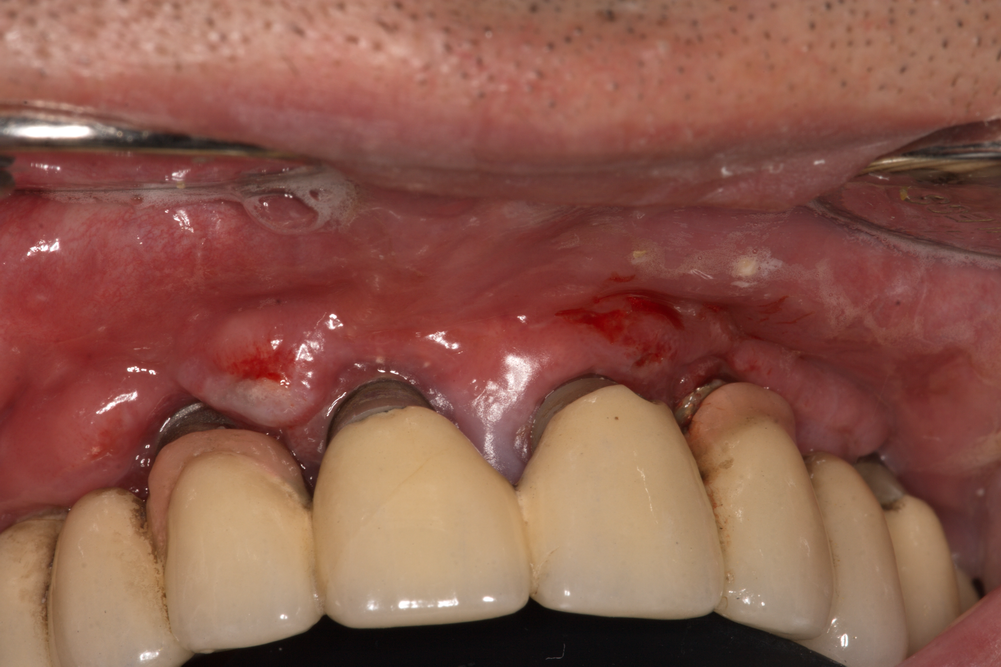

Обилно и продължително кървене при докосване на меките тъкани - клиничен белег за наличие на възпаление. Както вече стана въпрос, такива процеси протичат изключително бавно и при старание от страна на клинциста и пациента има предостатъчно време да бъдат овладени или поне стационирани. Затова периодичните контролни прегледи са от ключово значение за дългосрочните резултати от лечението със зъбни импланти. В случая на горната снимка пациентът не беше идвал на контролни прегледи за период от пет години след натоварвана на зъбните импланти с мостова конструкция. Анамнестично проблемите датират от около три години - периодично венецът се е подувал, изтичали са течности от венечната бразда, но поради заетост и поради липсата на болка пациентът не е идвал за клинични прегледи. Дори и при тази тежка клинична находка оплакванията на пациента не са силно изразени - болка на практика липсва, има единствено лош дъх от устата и изтичане на ексудат. Това е характерно за клиничната картина на периимплантита - бедна симптоматика особено от страна на пациента, съчетана със силно изразени клинични белези на възпаление, които обаче се откриват само от зъболекаря при преглед. Рентгенологичната находка е също доста показателна - тежка костна резорбция, особено при процеси с по-голяма давност.

Освобождаване на меките тъкани с цел да се формира достъп за почистване на гранулациите